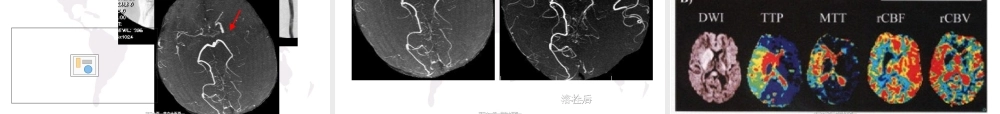

缺血性脑血管病CT、MRI新进展第一页,共六十五页。第一页,共六十五页。前言(qiányán)•脑卒中是目前世界范围内致残率、病死率最高的疾病之一。•我国在步入老龄化社会,脑卒中的发病率呈逐年上升趋势,发病年龄也趋于年轻化。•缺血性脑卒中占75-90%,多为非致命性,但致残率很高。•随着神经影像学的飞速发展,尤其是各种功能成像不仅能显示(xiǎnshì)形态学变化,还能提供脑血流、代谢等方面信息,对缺血性脑卒中的早期诊断和正确治疗及预防发挥重要甚至是决定性作用。第二页,共六十五页。第二页,共六十五页。一、急性(jíxìng)缺血性脑卒中•CT–急性脑卒中首选影像检查方法–区别出血和缺血性卒中的最好方法•急性缺血性脑卒中CT早期征象(<24小时,50~60%正常)–脑动脉高密度征:CT值77~89Hu(42~53Hu)–局部脑肿胀(zhǒngzhàng)征–脑实质密度减低征第三页,共六十五页。第三页,共六十五页。ClicktoaddTitle大脑大脑(dànǎo)(dànǎo)中中AA高密度高密度征征第四页,共六十五页。第四页,共六十五页。ClicktoaddTitle尾状核头豆状核岛尾状核头豆状核岛带边界带边界(biānjiè)(biānjiè)模糊模糊、、局部局部(júbù)(júbù)脑实质密度减低脑实质密度减低豆状核边缘豆状核边缘(biānyuán)(biānyuán)模糊模糊岛带消失征岛带消失征第五页,共六十五页。第五页,共六十五页。ClicktoaddTitle•ClicktoaddText第六页,共六十五页。第六页,共六十五页。局部局部(júbù)(júbù)脑肿胀脑肿胀第七页,共六十五页。第七页,共六十五页。急性(jíxìng)缺血性脑卒中•急性缺血性脑卒中进行早期溶栓治疗,尽快开通闭塞血管,可抢救缺血半暗带,获得较好疗效。•急性缺血性脑卒中CT早期征象阳性率低。•由于不同个体的循环(xúnhuán)和代谢储备能力不同,相同时间窗内,患者缺血半暗带千差万别。•单纯依靠缺血时间窗来间接推测是否存在缺血半暗带,有严重的局限性。第八页,共六十五页。第八页,共六十五页。急性(jíxìng)缺血性脑卒中多模式影像学检查multimodeimaging我们(wǒmen)非正式、简单地将后者称之为“CT全套或MR全套”CT全套:NECT(平扫)、PCT、CTAMR全套:T1WI、T2-flair、DWI、PWI、MRA/CE-MRA第九页,共六十五页。第九页,共六十五页。男,男,7272岁,岁,突然左侧突然左侧(zuǒcè)(zuǒcè)偏瘫半小时偏瘫半小时病例病例(bìnglì)(bìnglì)11第十页,共六十五页。第十页,共六十五页。病例病例(bìnglì)(bìng...

3、如文档内容存在违规,或者侵犯商业秘密、侵犯著作权等,请点击“违规举报”。